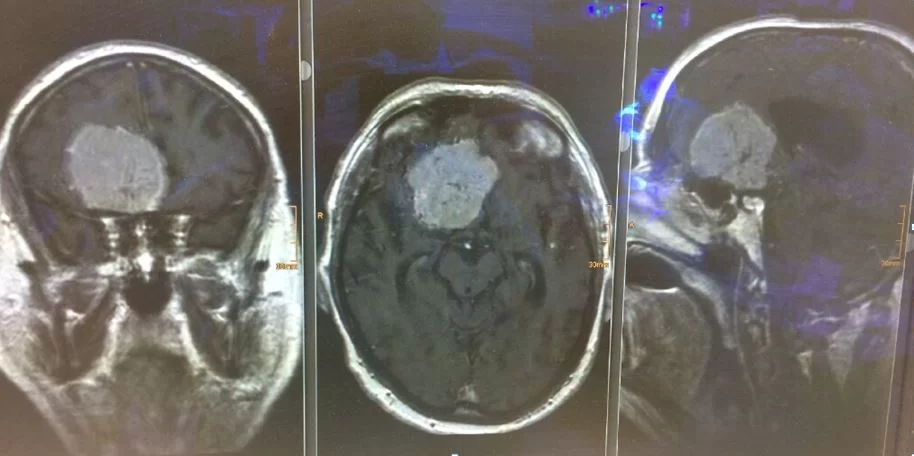

Στην παρακάτω εικόνα παραθέτω την περίπτωση ασθενούς με γιγαντιαίο μηνιγγίωμα το οποίο αφαιρέθηκε μέσα από υπερκόγχιο κρανιοτομία (τομή στο φρύδι). Το αν ο συγκεκριμένος όγκος είναι μεγαλύτερος ή μικρότερος απ’ αυτούς στους οποίους αναφέρεται το viral άρθρο είναι άγνωστο και εν’ τέλει – αδιάφορο.